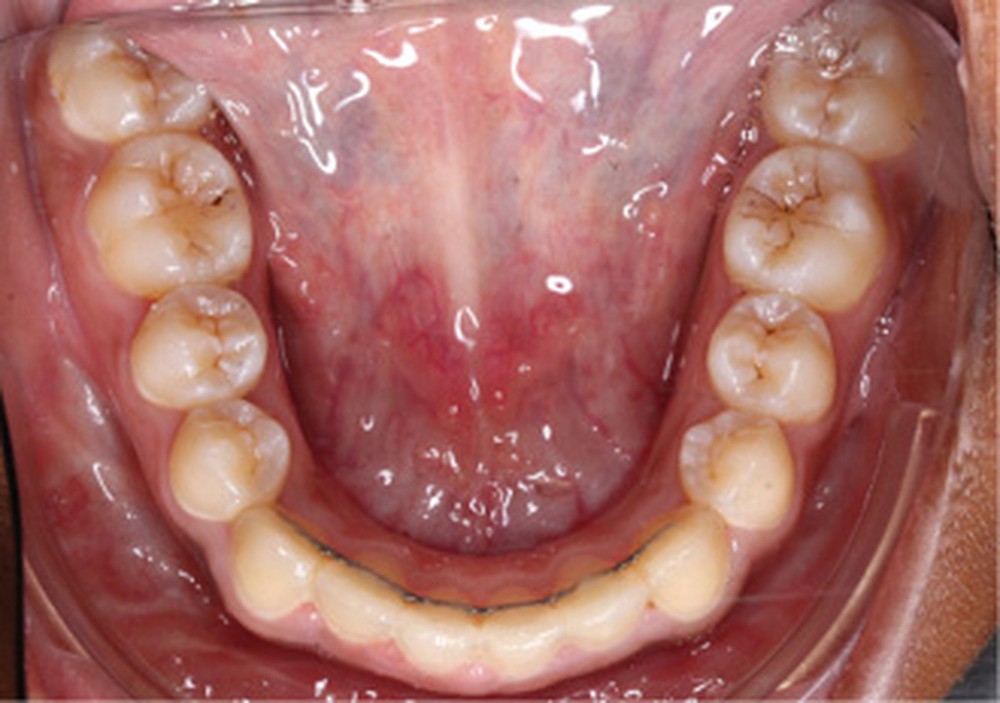

Examen clinique (fig. 1a-h)

L’arcade maxillaire est en V et la voûte palatine profonde. L’arcade mandibulaire a une forme en U (non-concordance des formes d’arcade) et présente des malpositions des dents cuspidées. La médiane mandibulaire est décalée à gauche de 2 mm ; le recouvrement antérieur est de 2 mm ; les molaires sont en classe III avec un surplomb inversé.